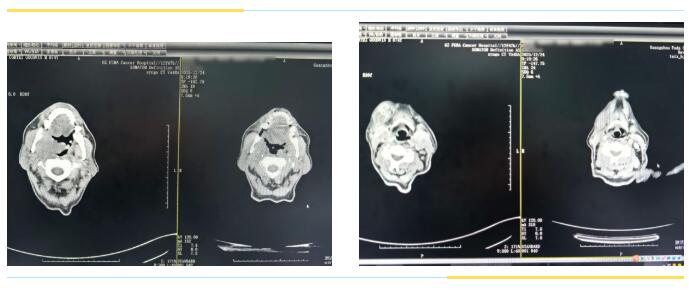

△两个疗程后的CT对比图,口咽肿物、颈部肿块缩小